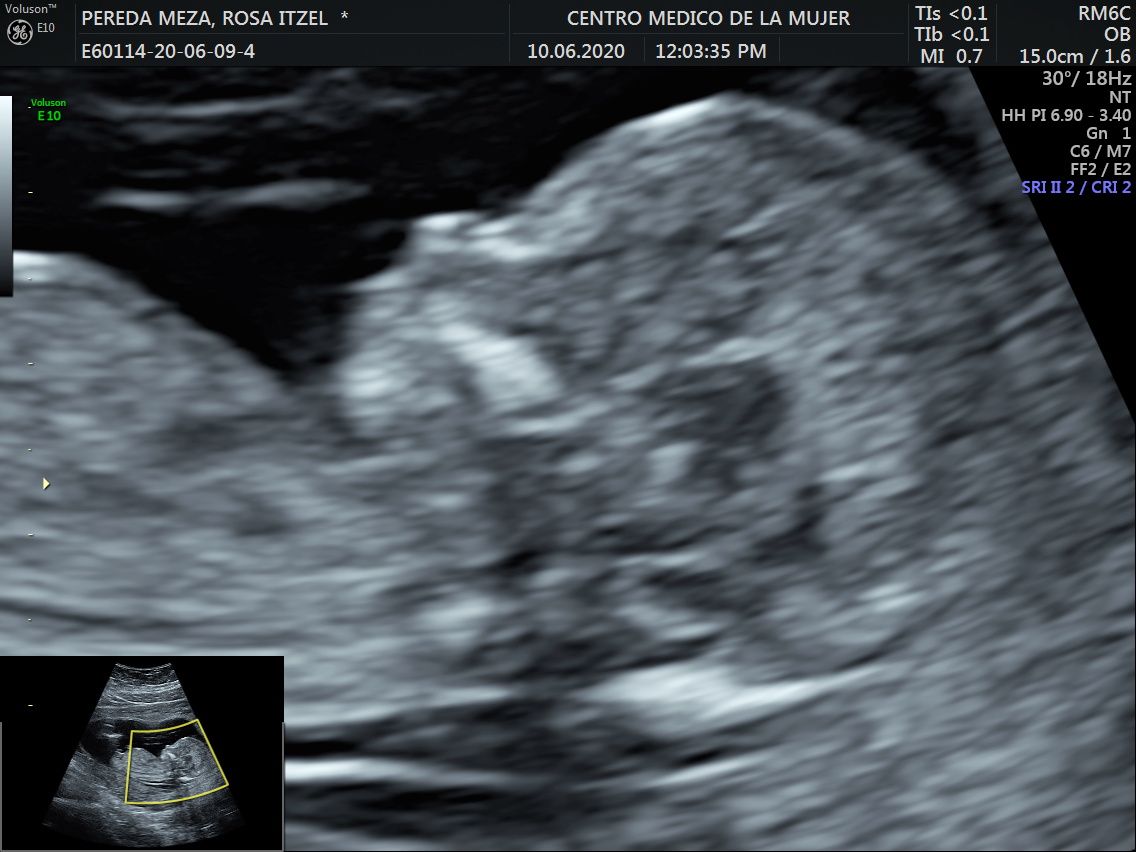

Fotos y videos

ECO Anatómico

Consiste en la evaluación especifica de cada organo y sistema del bebé con medidas detalladas de cada parte para evaluar su crecimiento proporcional.